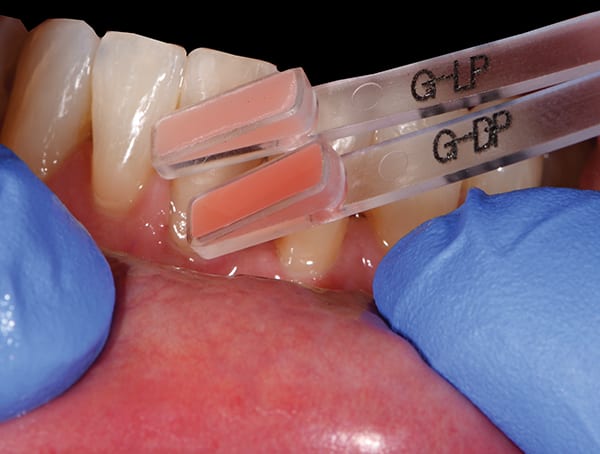

Black triangles in cervical embrasure areas are unesthetic and often cause patients to have difficulty with phonetics and hygiene. A 66-year-old woman presented to the periodontal office of Dr. Jason Stoner with excessive bleeding in the mandibular anterior region. She had a history of trauma to teeth Nos. 24 and 25 years prior, which were endodontically treated at the time of injury. Dr. Stoner's evaluation revealed a large resorptive defect on the distal extent of tooth No. 24. After considering different treatment options, the patient opted for removal of No. 24 and orthodontic therapy to achieve space closure post-extraction. Prior to removal of the tooth, Drs. James Hutta and Jeff Price were added to the treatment team to assist with orthodontics. Dr. Stoner extracted tooth No. 24 without complication, and the orthodontic phase took approximately 18 months. Upon completion of orthodontics a large residual black triangle remained between teeth Nos. 23 and 25. At this time, the patient's previous restorative dentist placed composite bonding, which the patient was not happy with. She then was referred to the author's office for evaluation of the residual Miller Class III defect. Exploiting the many benefits of bioactive Giomer Technology (Shofu, shofu.com), the author developed a treatment plan that would utilize both pink Giomer and white composite to satisfy the treatment objectives.

Shofu's Beautifil® II Gingiva with Giomer Technology offers numerous benefits in terms of biology and esthetics in the treatment of Miller Class III and IV defects.

This use of pink Giomer and white composite bonding is a conservative option for the correction of black triangles.